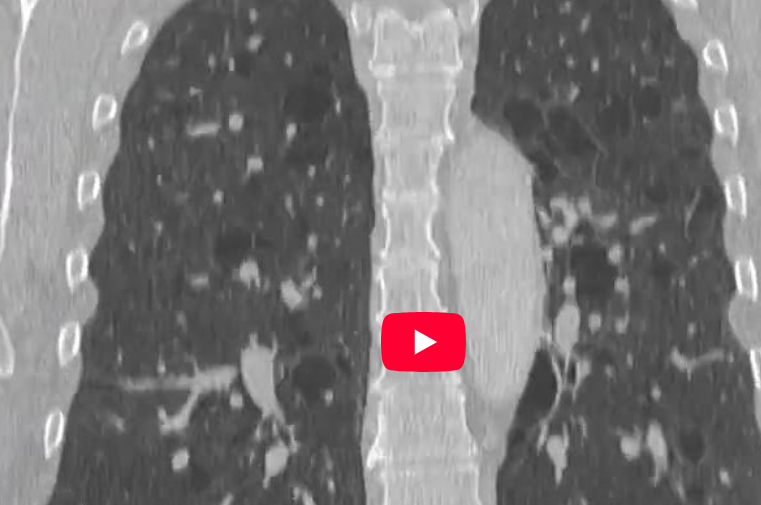

CAZ nr 115: Limfangioleiomiomatoză (LAM) pulmonară

Video 3: reconstrucție coronală CT în fereastră de plămân la nivel toracic, examinare efectuată în inspir

Discuţie caz nr 115: la nivelul ambelor parenchime pulmonare se evidențiază leziuni rotund-ovalare de tip chistic, cu perete subțire, dispuse difuz si relativ uniform.

DE LUAT ACASĂ!!! LAM este o boală sistemică rară care apare sporadic au în cadrul sclerozei tuberoase și se caracterizează prin proliferarea anormală a unor celule musculare netede. Caracteristica principală a limfangioleiomiomatozei (LAM) la examenul tomografic este prezența unor chisturi multiple, bilaterale, cu pereți subțiri, rotunjite, distribuite uniform în ambii plămâni, adesea cu parenchim pulmonar normal intermediar, în special în stadiile incipiente ale bolii. Chisturile variază în dimensiuni, de obicei 2-30 mm, și pot crește progresiv și deveni mai numeroase în stadiile mai avansate ale bolii.